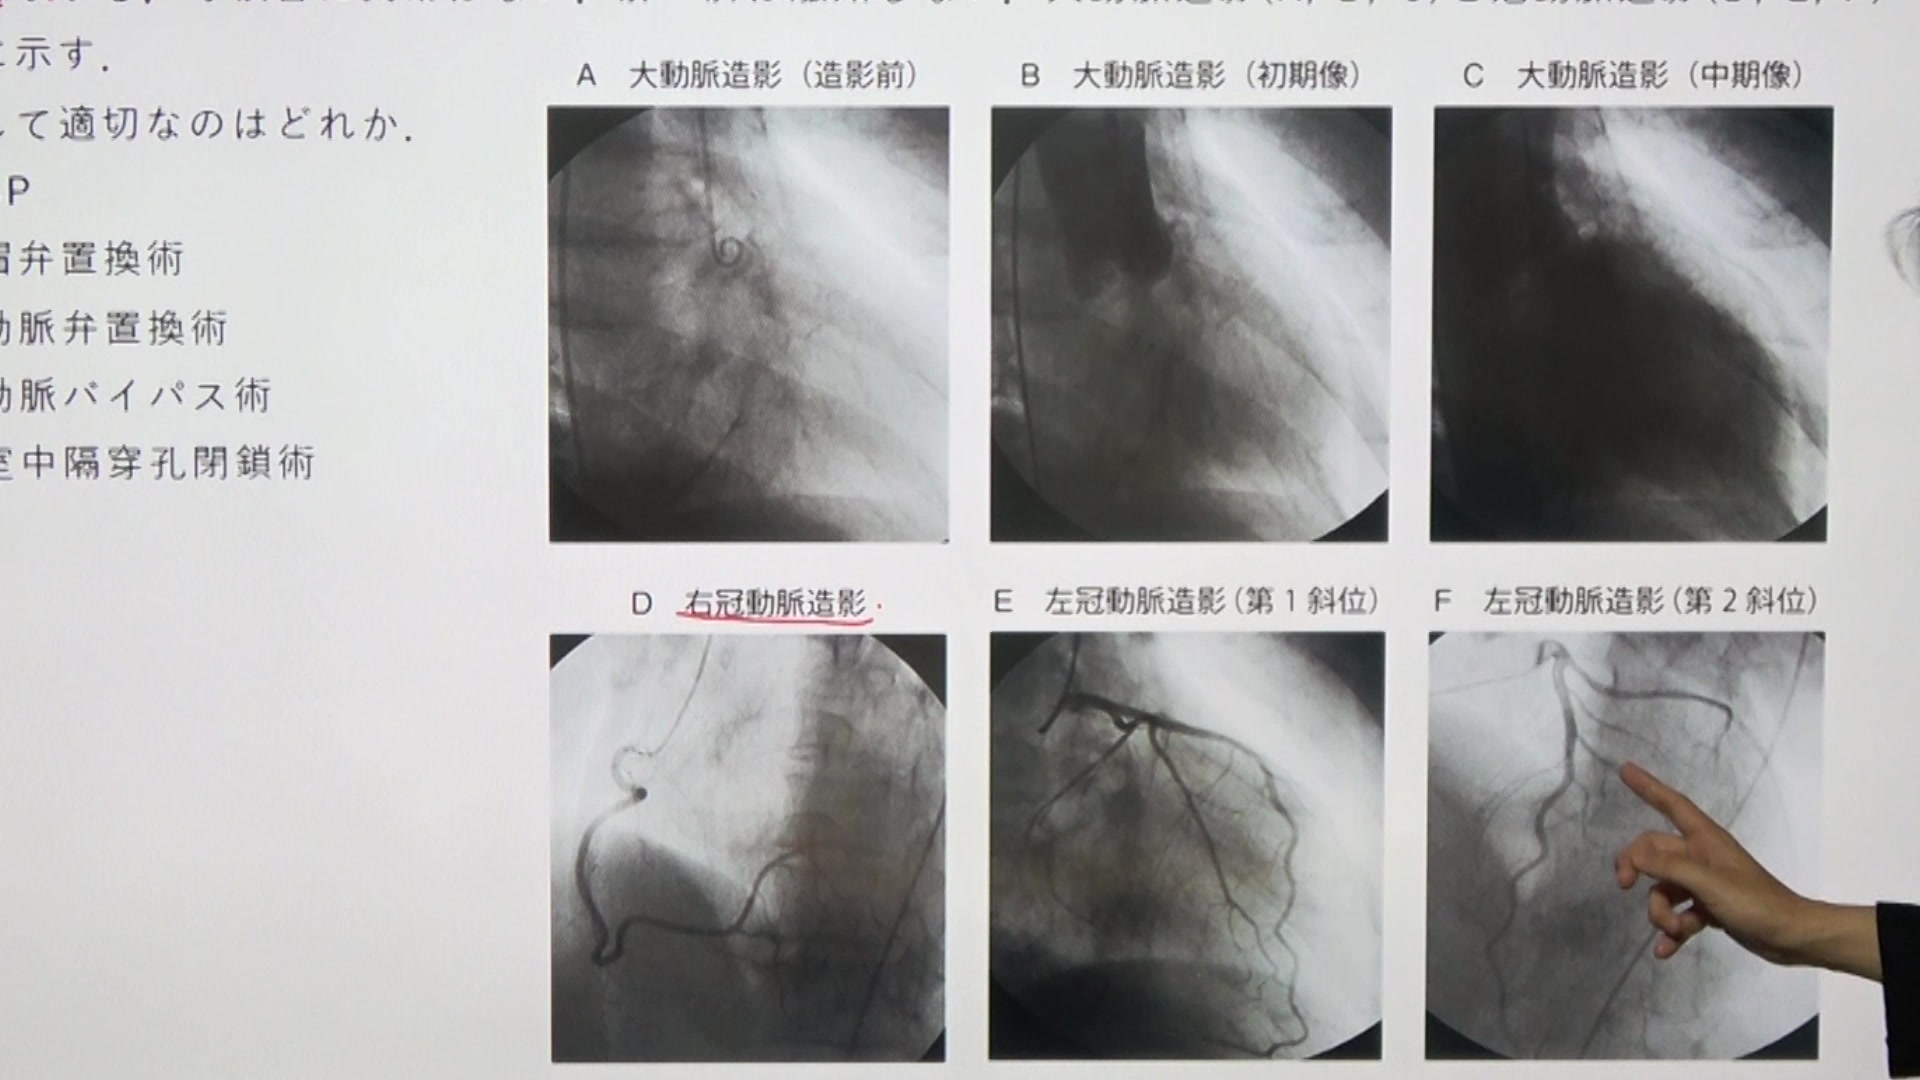

大動脈弁狭窄症

C05 大動脈弁狭窄症 問題12~16